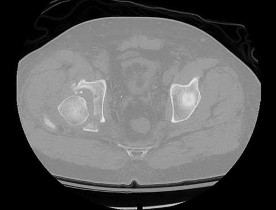

A 42-year-old male is brought to the trauma bay after a crush injury. Pelvic radiographs show widening of the pubic symphysis of 3.5 cm and disruption of the anterior sacroiliac ligaments, but intact posterior sacroiliac ligaments. According to the Young-Burgess classification, which type of pelvic ring injury does this represent?

Correct Answer: APC II

Explanation:

The Young-Burgess classification divides anteroposterior compression (APC) injuries into three types. APC I: symphysis widening <2.5 cm with intact SI ligaments. APC II: symphysis widening >2.5 cm with disruption of the anterior SI, sacrotuberous, and sacrospinous ligaments, but INTACT posterior SI ligaments (rotationally unstable, vertically stable). APC III involves complete disruption of anterior and posterior SI ligaments.